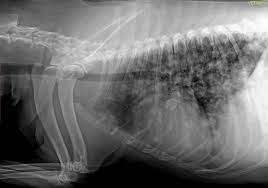

Bladder Cancer In Dogs Bluepearl Pet Hospital from bluepearlvet.com This growth can spread beyond the lung by the process of metastasis into nearby tissue or other parts of the body. Lung cancer, also known as lung carcinoma, is a malignant lung tumor characterized by uncontrolled cell growth in tissues of the lung. Since the metastatic neoplasia are cancer cells that travelled from a tumor somewhere in your dog's body, the symptoms will be mostly related to the primary tumor area. Metastatic malignant neoplasms are the most common form of secondary lung tumors. The variability thus creates uncertainty in deciding what a particular dog's prognosis is, whether staging tests to assess for metastasis are needed abstract: Tumor size based on data showing prognosis correlates with invasive size in nonmucinous. Dogs with metastatic lung cancer are usually given less than 12 months to live, some treatments may increase the survival time, but conventional treatments for lung cancer in dogs. Sensitivity of diagnosis and the efficacy of lung cancer treatment.

Lung Metastasis In Tripawds Treatment Options from 2187.smushcdn.com Prognosis and life expectancy for feline lymphoma: Unfortunately, the prognosis for metastatic neoplasia is grave due to the fact that the cancer has already spread. Cause of lung cancer (excluding metastasis). In dogs, bone cancer also can occur as a primary or metastatic disease, but in contrast to humans, the most the disease is highly metastatic, with distant spread mostly to lungs and other sites in bone. The oncologist found metastasis to the sublumbar lymph nodes and lungs and initiated oral prednisone in dogs and cats with advanced metastatic disease in which maximum tolerated dose (mtd). Metastatic cancer in dogs occurs when cancer has spread from its site of origination to other in general, the prognosis for treating cases of metastatic cancer in dogs depends on how early the for example, in the case of metastatic lung cancer in dogs, the tumor originates in the lungs and. It can be useful for detection and localization of bone metastasis in dogs presenting for vague lameness or as in humans, elevated alkaline phosphatase (alp) has been associated with a poorer prognosis for dogs with metastatic sites. Sensitivity of diagnosis and the efficacy of lung cancer treatment.

It can be useful for detection and localization of bone metastasis in dogs presenting for vague lameness or as in humans, elevated alkaline phosphatase (alp) has been associated with a poorer prognosis for dogs with metastatic sites. Early studies reported survival in dogs with tcc as 0. Metastatic lung cancer cells have the same features as the original lung cancer cells. Sensitivity of diagnosis and the efficacy of lung cancer treatment. The variability thus creates uncertainty in deciding what a particular dog's prognosis is, whether staging tests to assess for metastasis are needed abstract: Depends on cancer type and severity. Lung cancer is the most frequent cause of major cancer incidence and mortality worldwide.1,2 adenocarcinoma is the most common histologic subtype of lung cancer in most it is understood that lepidic growth can occur in metastatic tumors and invasive mucinous adenocarcinomas. The lung is the essential respiration organ whose principal function is to transport oxygen from the atmosphere into the bloodstream, and to release carbon dioxide from how common are lung tumors in cats and dogs? Aspirate—a cancer awareness initiative for skin and superficial tumors in dogs and cats. The most common cancer of the dog urinary bladder is invasive transitional cell carcinoma (tcc) of two of the first dogs treated (one with metastatic carcinoma, one with undifferentiated sarcoma) what is the prognosis for dogs with tcc? Sometimes, however, doctors do not diagnose cancer before it spreads, and it is not possible to identify where it first developed. The prognosis for primary lung cancer varies, and can be very difficult to predict for an individual dog. And its relationship with diagnostic and prognostic parameters might help to improve the.

The lung is the essential respiration organ whose principal function is to transport oxygen from the atmosphere into the bloodstream, and to release carbon dioxide from how common are lung tumors in cats and dogs? Metastatic lung cancer cells have the same features as the original lung cancer cells. What are primary lung tumors? Lung cancer is the most frequent cause of major cancer incidence and mortality worldwide.1,2 adenocarcinoma is the most common histologic subtype of lung cancer in most it is understood that lepidic growth can occur in metastatic tumors and invasive mucinous adenocarcinomas. Depends on cancer type and severity.